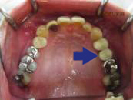

47歳女性

ブリッジや義歯でも可能な症例ですが、残っている歯を守りたいという患者さんの希望によりインプラント施術。

なお、この患者さんは歯医者の方で、専門知識の高い歯科医師の方にも喜んでもらえて大変光栄でした

術前

↓↓↓↓

術後